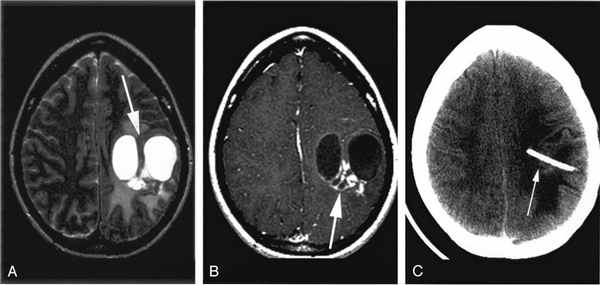

55. ДАП (диффузные аксональные повреждения).

Тяжелая ЧМТ. Характерно распределение точек

максимального повреждения вдоль трактов белого

вещества головного мозга.

Локализация 2/3 очагов субкортикальная, часто лобнопарасагиттальная, височно-перивентрикулярная, менее

часто теменная и затылочная области. Вовлечение

(всегда) мозолистого тела (валик, и задние отделы

корпуса). Могут быть внутрижелудочковые геморрагии.

Травматическое повреждение таламусов и базальных

ганглиев относительно непостоянны.

Негеморрагические.

В остром периоде – наличие небольших участков отека,

через несколько дней возможно присоединение

геморрагического компонента.

Геморрагические.

мелкие внутримозговые гематомы с типичной фазовой

трансформацией.